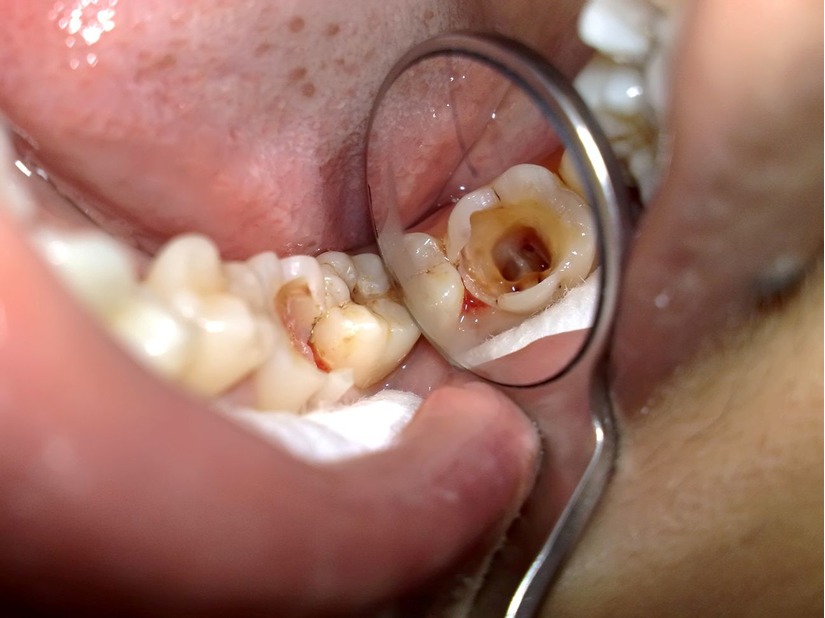

Tủy răng bị viêm, hư tổn là một dạng bệnh lý phổ biến ở răng miệng do một trong các nguyên nhân sau gây ra:

- Răng bị mẻ vỡ, nứt gãy.

- Răng bị vi khuẩn xâm hại, sâu răng lâu ngày không được điều trị.

- Các răng bị chấn thương bị đứt mạnh máu nuôi tủy răng.

- Những răng bị mòn, viêm quanh răng.

- Răng sâu, mẻ vỡ, nứt gãy là những nguyên nhân dẫn đến viêm tủy răng